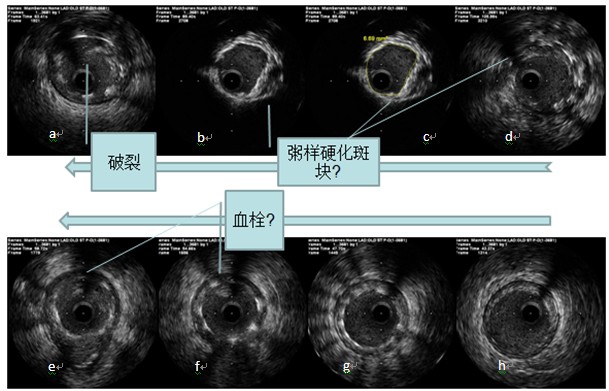

a图3 支架内狭窄病变扩张后发生无复流的IVUS影像 |

图3显示:a~h为自前降支支架近段到支架远端的影像,a图可见支架内夹层,可见内膜片突入(可能是球囊扩张引起);b和c可见支架内增生组织内膜面回声增强,其后可见大片密度减低区,组织显影不清,支架梁影可能在此区域内,显示不清,在2点到6点区域影像类似脂质斑块;此处面积最窄,管腔面积6.69mm2;d图支架内增生组织密度低,表面覆盖一层高密度组织,可疑脂质斑块;图e和f可见突入管腔的不规则阴影,可疑血栓,图g支架膨胀良好,支架内未见明显增生组织,图h支架边缘大致正常管腔,可见轻度斑块,未见夹层及壁下血肿。

因是在球囊扩张后的影像,故考虑之前斑块可能是富含脂质的斑块伴有血栓,在扩张后导致大量脂质成分或血栓到达远端,造成栓塞、激发炎症反应、痉挛、内皮水肿等引起无复流。之后继续冠脉内间断应用硝酸甘油等药物,血流最终恢复至接近3级,返回病房。